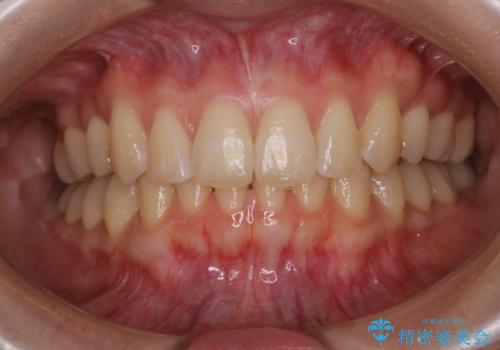

オフィスホワイトニング(エクセレントコース)

- オフィスホワイトニング希望で1日で白くしたいとのことでした。

オフィスホワイトニングのエクセレントコース(¥29700)を行いました。

担当

表参道しらゆり歯科 DH西澤